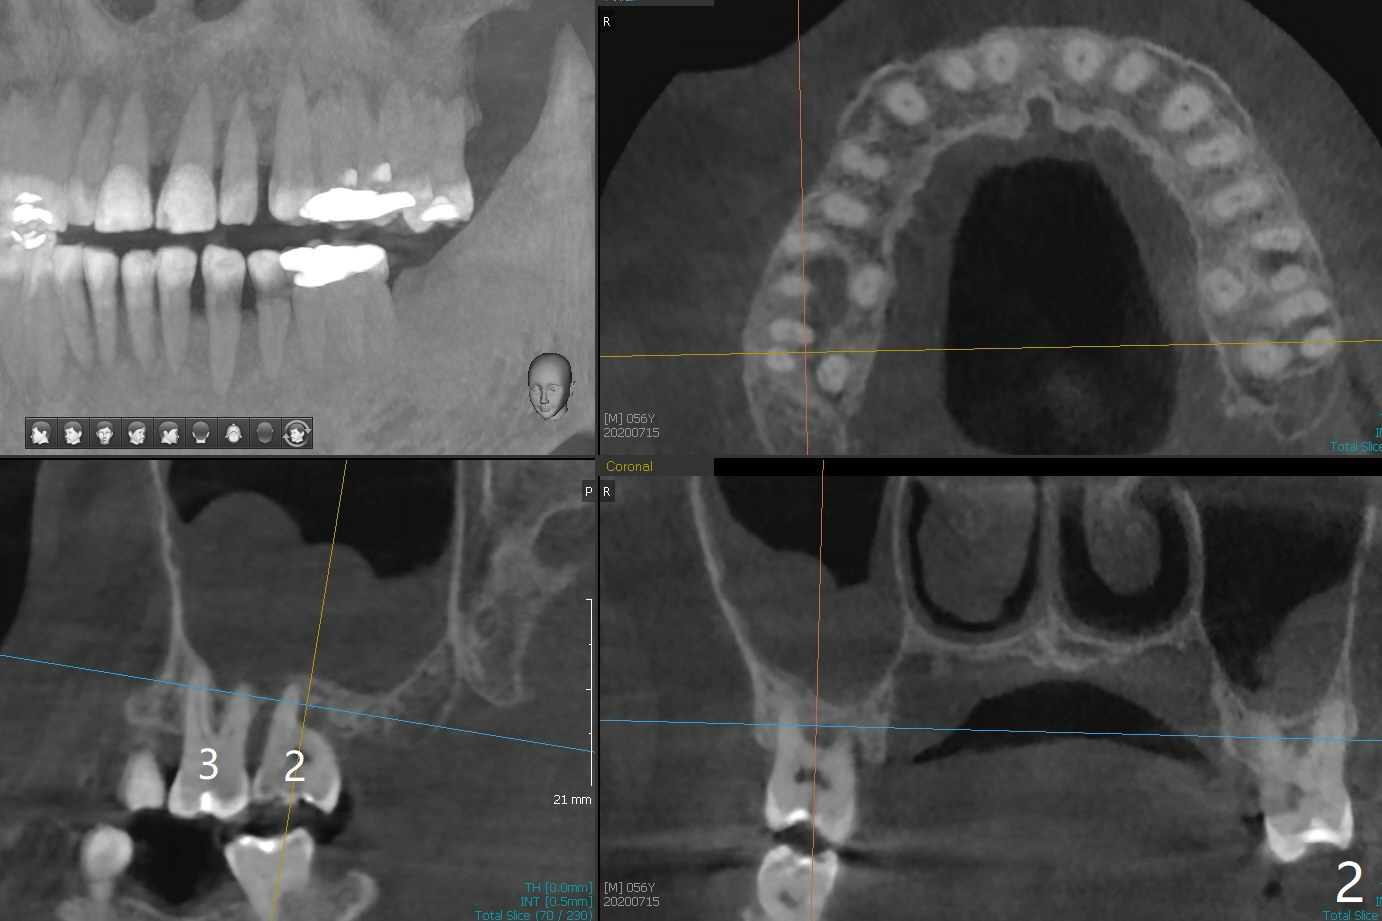

A 56-year-old man (smoker) has pain at #2 (Fig.1-3 thickened sinus membrane (R>L), C: mucous retention cyst) associated with subgingival crack (Fig.4 arrowheads). A 5x8.5 mm implant will be immediately placed with sinus lift aided by PRF membrane (Fig.5). A narrow implant will be placed at #30 (Fig.6).